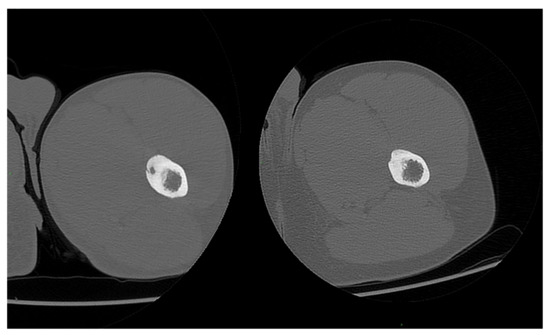

3. Results